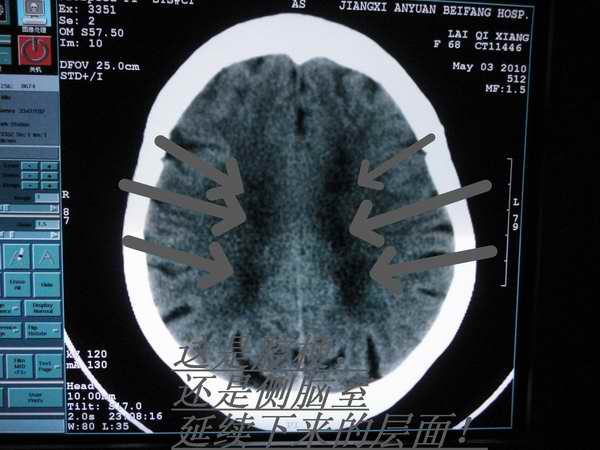

f68岁,突然头晕呕吐咖啡色胃内容物,反复半天伴双下肢行走不利,原有高血压史

箭头所指是腔梗病灶,还是侧脑室延续下来的层面!

1)多发性腔隙性脑梗塞。2)脑萎缩。3)脑白质病。